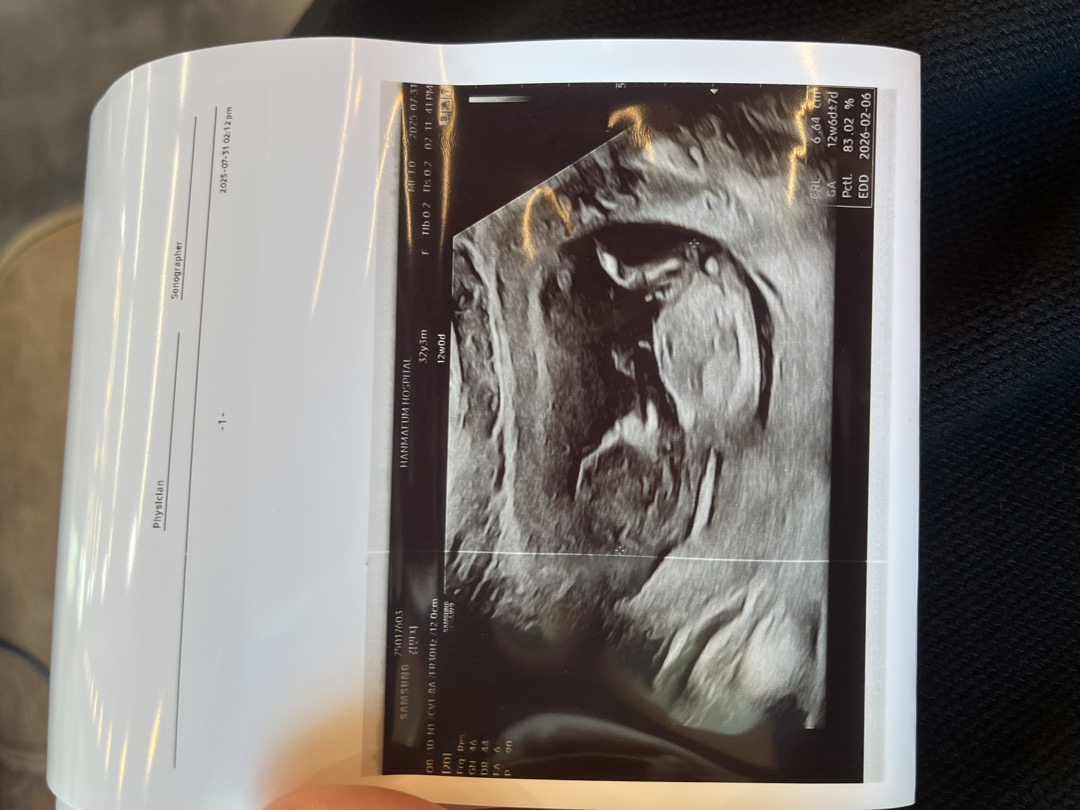

12주 각도법 알려주세요~~^^

너무 궁금한데 병원에서 안 알려줬어요 😂😂